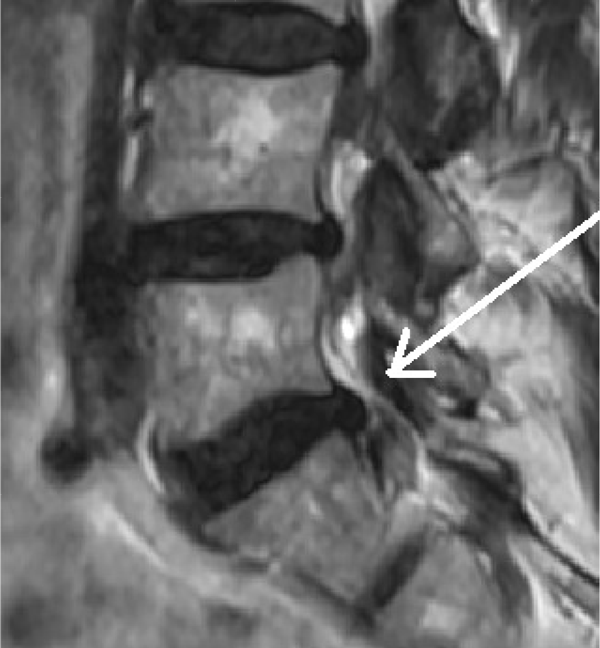

Die folgenden MRT Bilder stammen von einem Patienten mit Bandscheibenvorfall L5/S1. Der Patient ist vorher mehrere Monate arbeitsunfähig gewesen und wurde mit diversen konventionellen Verfahren erfolglos behandelt. Als nächster Schritt wäre eine OP angestanden, die mit der SpineMED® Therapie verhindert werden konnte. Sollten Sie Fragen haben, zögern Sie nicht uns zu kontaktieren, wir bemühen uns um einen Zeitnahen Termin für Sie, und beantworten alle Fragen gerne.

Nach Spinemed